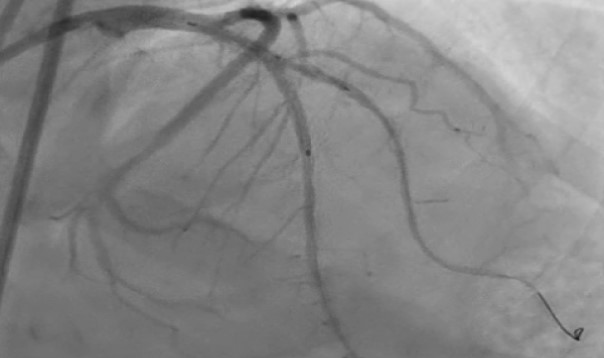

1) Proximal Left Anterior Descending artery's pre analysis done with OCT.2) Calcium arc on OCT displayed as 360 degrees with 800 micron thickness and length greater then 5mm with minimum Lumen Area of 1.83mm3) Intravascular Lithotripsy performed with focus on proximal Left Anterior Descending Artery4) Post Intravascular Lithotripsy procedure, Optical Coherence Tomography was performed5) The lumen gain obtained post procedure was equivalent to 5.24mm6) Stenting done7) LCX ostium with tight lesion with heavy calcification pre dilated with NC balloon and two stents placed.

Case Summary

Imaging plays a major role in choosing the correct modality for dealing with heavily calcified lesion. IVL gives the result while dealing with superficial to deep calcium. The nodular calcium at LCX ostium can be managed with NC balloon and stenting.